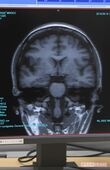

ライターのMRI画像

[写真 3/3枚目] ライターのMRI画像